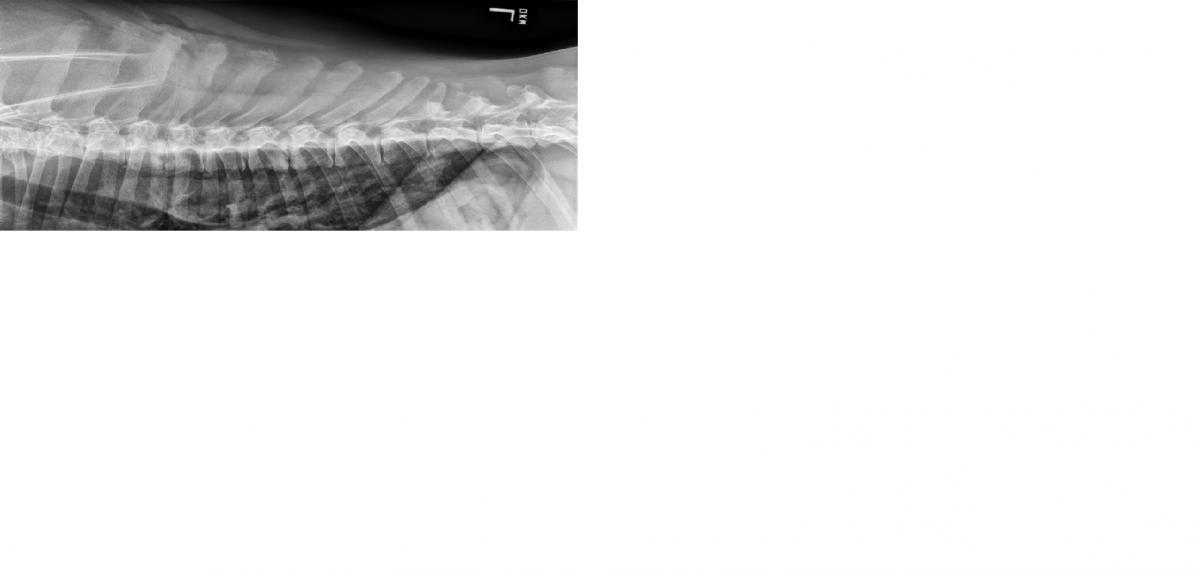

This radiograph is from a 4 year old FS great dane who presented for evaluation of persistent stiff gait and lethargy. Interpret the radiograph below.

This is a lateral cervicothoracic radiograph. There is evidence of end plate lysis at C5-6, T1-2, T3-4, T4-5, T7-8, and possible slight change at T9-10 as well. There is also disc space collapse affecting most of the thoracic spine between T1 and T9. Ventral vertebral spondylosis is also appreciated from T4-5 (most significant) to T7-8 (slight). These changes are most consistent with discospondylitis. The following series of radiographs are from the same patient. Aspiration of the L1-2 disc space produced Phialosimplex fungal organism on culture. The dog’s signs have been controlled on Voriconazole.

Note the multifocal distribution including sternal involvement which may be more likely seen with fungal disease.